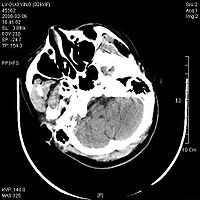

脑干损伤CT图

8.CT扫描 是目前辅助诊断颅脑损伤的重要依据。能显示颅骨骨折、脑挫裂伤、颅内血肿、蛛网膜下腔出血、脑室出血、气颅、脑水肿或脑肿胀、脑池和脑室受压移位变形、中线结构移位等。病情变化时应行CT复查。

9.MRI 急性颅脑损伤患者通常不作MRI检查。但对病情稳定的弥漫性轴索损伤、大脑半球底部、脑干、局灶性挫裂伤灶和小出血灶、等密度亚急性颅内血肿等,MRI常优于CT扫描。

2.颅脑CT、MRI扫描 原发性脑干损伤表现为脑干肿大,有点片状密度增高区,脚间池桥池四叠体池及第四脑室受压或闭塞。继发性脑疝的脑干损伤除显示继发性病变的征象外,还可见脑干受压扭曲向对侧移位,MRI可显示脑干内小出血灶与挫裂伤,由于不受骨性伪影影响,显示较CT清楚。